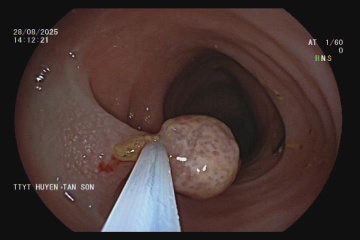

Mắc ung thư đại trực tràng ở tuổi 25

Những cơn rối loạn tiêu hóa âm thầm suốt 4 năm, đến khi đau bụng dữ dội nhập viện, Xuân Quang sốc khi biết anh là bệnh nhân ung thư đại trực tràng ở tuổi chưa tròn 30.

Bé gái 9 tuổi được phát hiện có 4 polyp trực tràng khi nội soi gây mê. Đây là trường hợp hiếm gặp, cho thấy nguy cơ ung thư đại trực tràng không chỉ dừng ở người lớn.